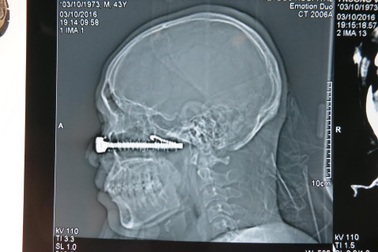

Xuyên đêm cấp cứu bệnh nhân bị đinh vít sắt đâm xuyên mặtTai nạn trong chớp mắt đã khiến một chiếc đinh vít (kèm móc sắt) dài tới hơn10 cm găm xuyên qua mặt một người đàn ông sát ngay dưới một bên mắt. Một cuộc hội chẩn liên viện giữa bệnh viện (BV) Việt Đức và BV Mắt Trung ương nhanh chóng diễn ra tại BV Việt Đức sau khi tiếp nhận bệnh nhân.